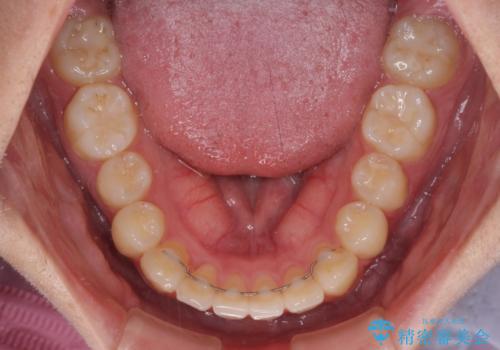

- 八重歯を気にして来院された高校生の患者様です。

ボディーコンタクトの激しい部活動を行っているため、補助装置とインビザラインを用いて、部活動を継続しながら治療を行うこととしました。

八重歯を効率よく改善するため、補助装置を使用して上顎の奥歯を後方に移動させました。

部活動をしながらでしたが、マウスピースをしっかりと装着してくださったので、1年半程度で終了することができました。